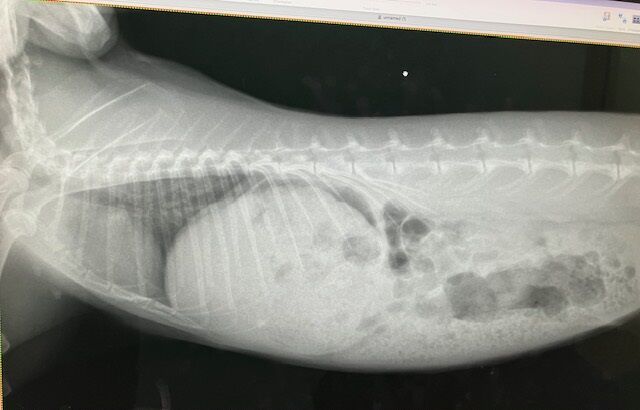

術前の血液検査、レントゲン、いずれも問題ありません。

※白血球の上昇などはストレス起因と判断できるレベル、と、

血小板は機械の誤作動による、顕微鏡で別途確認済

奥歯も問題なし。

12月4日、ドナちゃん避妊手術しました。